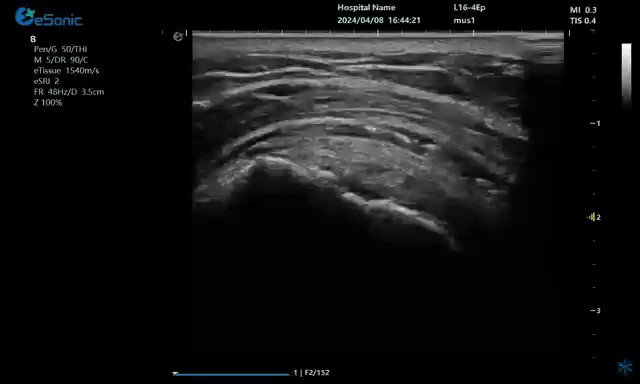

二、超声引导下注射准确性的临床验证及临床疗效研究

通过CT影像手段也验证了超声引导下注射的准确性。

超声引导下注射临床效果是否优于无超声引导下注射,部分研究显示了这方面的结果。